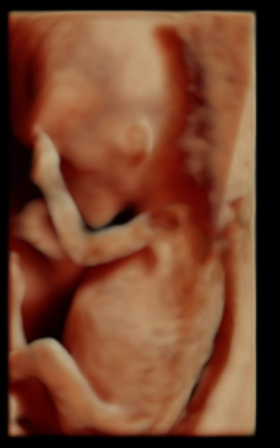

Наш 1 скрининг в 12 недель ♥️

Всё о нашей беременностиНаконец то дождались 1 скрининга, все у нас хорошо)) ттт🙏узистка сказала 70 % что будет девочка, я счастлива, муж сказал что все равно надеется что будет сын) мы ходили вместе, сказал что он успел разглядеть там пипеньку😂все узи крутилась, отварачивалась,закрывала лицо ручками))ну или закрывал))

Спасибо) да это у нас узи студия, там и 3д и обычное узи делают за раз в разных режимах смотрят)) у нас ктр не очень большой 4.9, мы на 2 дня немножко отстаем в размере)